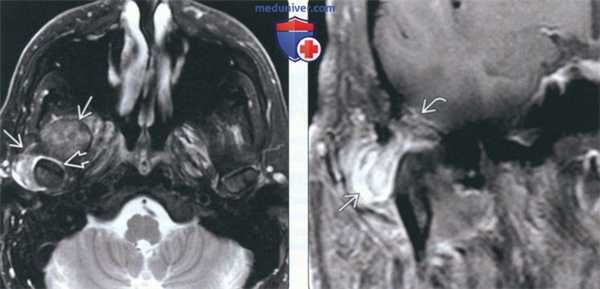

(Слева) На аксиальной МРТ (Т2 ВИ FS) у пациента с болезнью накопления КПФД вокруг компонентов правого ВНЧС визуализируется неоднородное объемное образование с преимущественно гипоинтенсивным сигналом. Обратите внимание на гиперинтенсивную жидкость в суставном пространстве вокруг мыщелка нижней челюсти.

(Справа) На корональной MPT (Т1 ВИ С+) у этого же пациента определяется контрастное усиление объемного образования в нижних наружных отделах. Обратите внимание на дефект крыши суставной ямки и легкое контрастирование твердой мозговой оболочки. Интракраниальное распространение отсутствует.